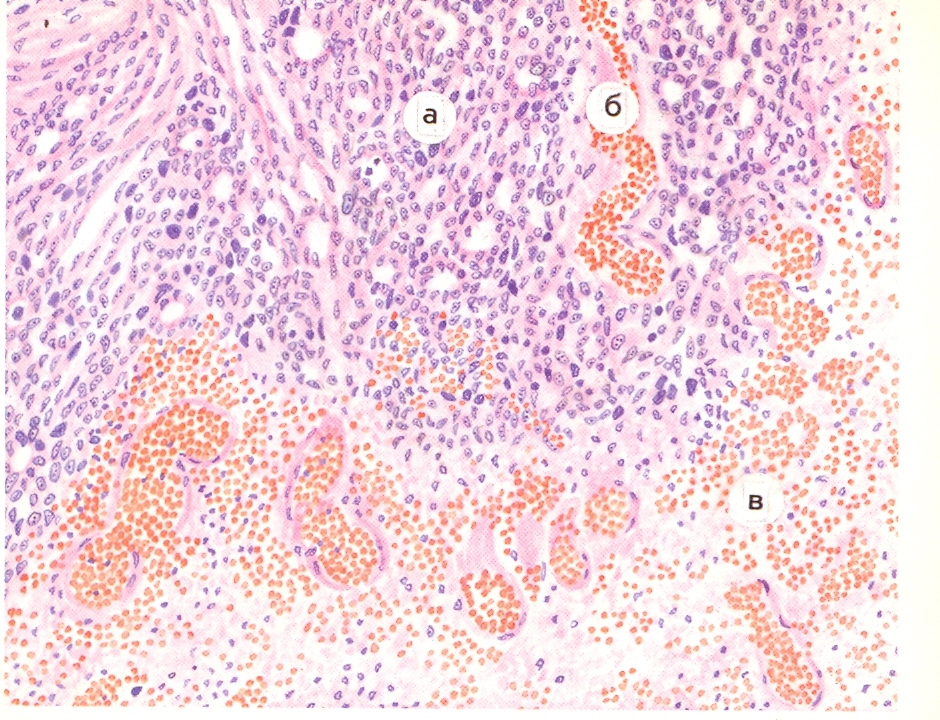

Микрофотографии гистологии глиобластомы головного мозга